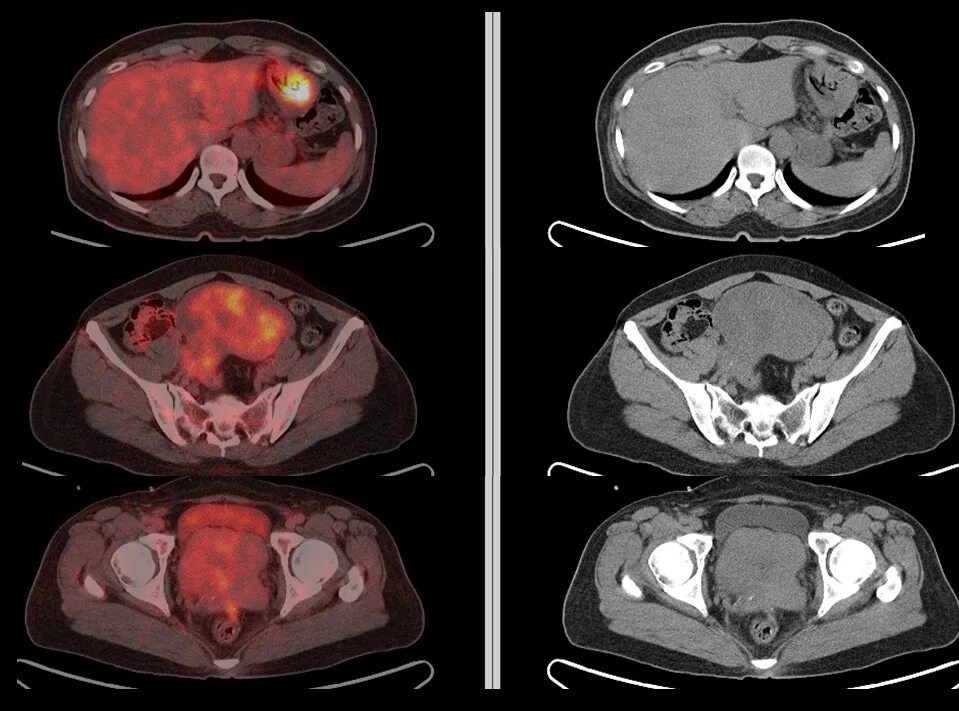

Вероятность метастаз